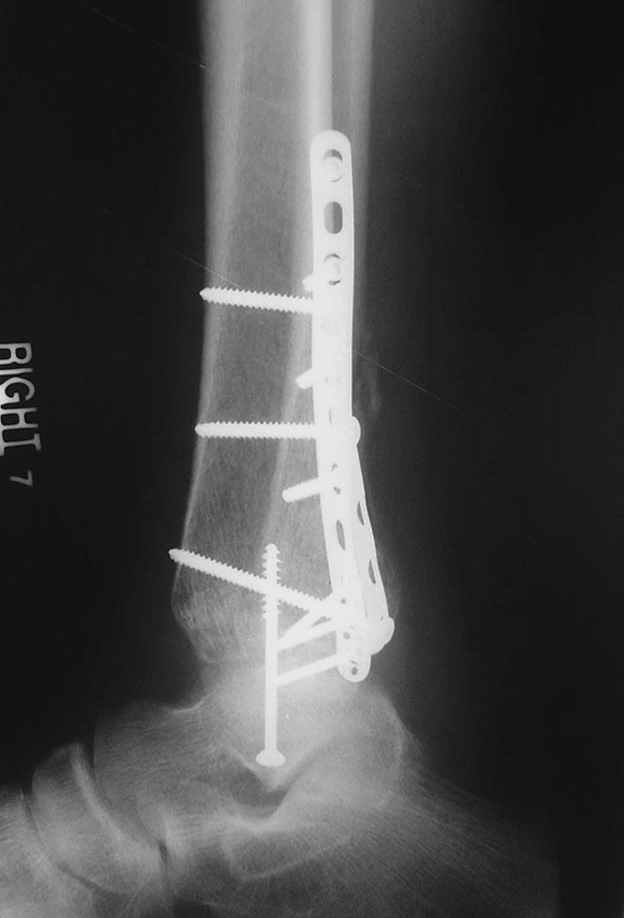

Второй случай сделан из одного разреза

ЕЧ LISS plate, mininvasive approach - luxurous !

Вопрос практического характера - такой подход рутинный или при определенных показаниях и каких? Спрашиваю потому, что при потоке больных - закрытая голень, бедро, голеностоп и т.д. лучевая нагрузка должна быть немалая, каковы показатели дозиметра после такого операционного дня и при 2-3 операционных днях в неделю по 5-6 случаев (не считая ургентностей)?

С точки зрения : Сгорая сам - свети другим :-)) это вполне понятно, но личная практика показывает, что далеко не все пациенты относятся волнительно и критично к длине кожного разреза. Подозреваю, что это и есть критерий при выборе техники фиксации?

На прямой проекции послеоперационного Рг макроскопически все выглядит очень анатомично, при микроскопическом ( :-)) ) рассмотрении можно все-таки заметить вальгизацию тарана, суставная щель в латеральном отделе сустава несколько уже , чем в медиальном при отсутствии латерального смещения тарана. У меня был аналогичный случай (без LISS , без мини доступа) с вальгусным наклоном тарана при восстановленном ankle mortise при последовательном наблюдении с интервалами в 6-8 недель в послеоперационном периоде отмечалось прогрессирующее сужение суставной щели в латеральном отделе сустава, закончившееся посттравматическим ОА, к счастью боли умеренные, купируемые аналгетиками или своими эндорфинами:-))(активная пациентка, у которой нет времени на болезни....) Какова жизненная ситуация в приведенном вами случае? И последнее, что я хотел бы прояснить для себя - фиксация внутренней лодыжки: я обычно комбинирую фиксацию компрессирующим винтом со спицей - по идее ротационная стабильность должна быть лучше, чем один винт, каковы ваши наблюдения в этом плане?